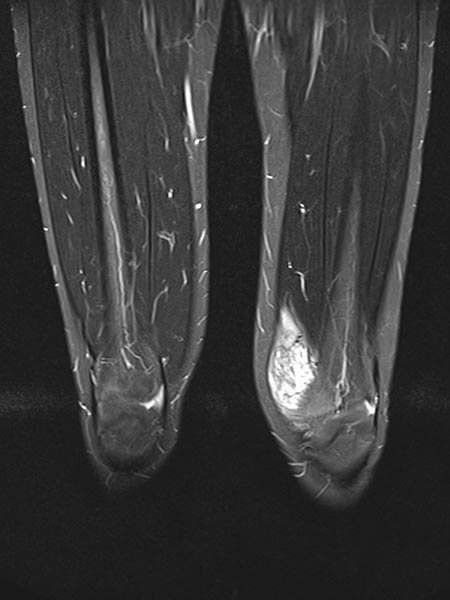

In der koronaren T2-gewichteten, fettunterdrückten MRT wiederum typisches Bild einer stark hyperintensen venösen Malformation mit deutlicher Ausdehnung auch in kranio-kaudaler Richtung.